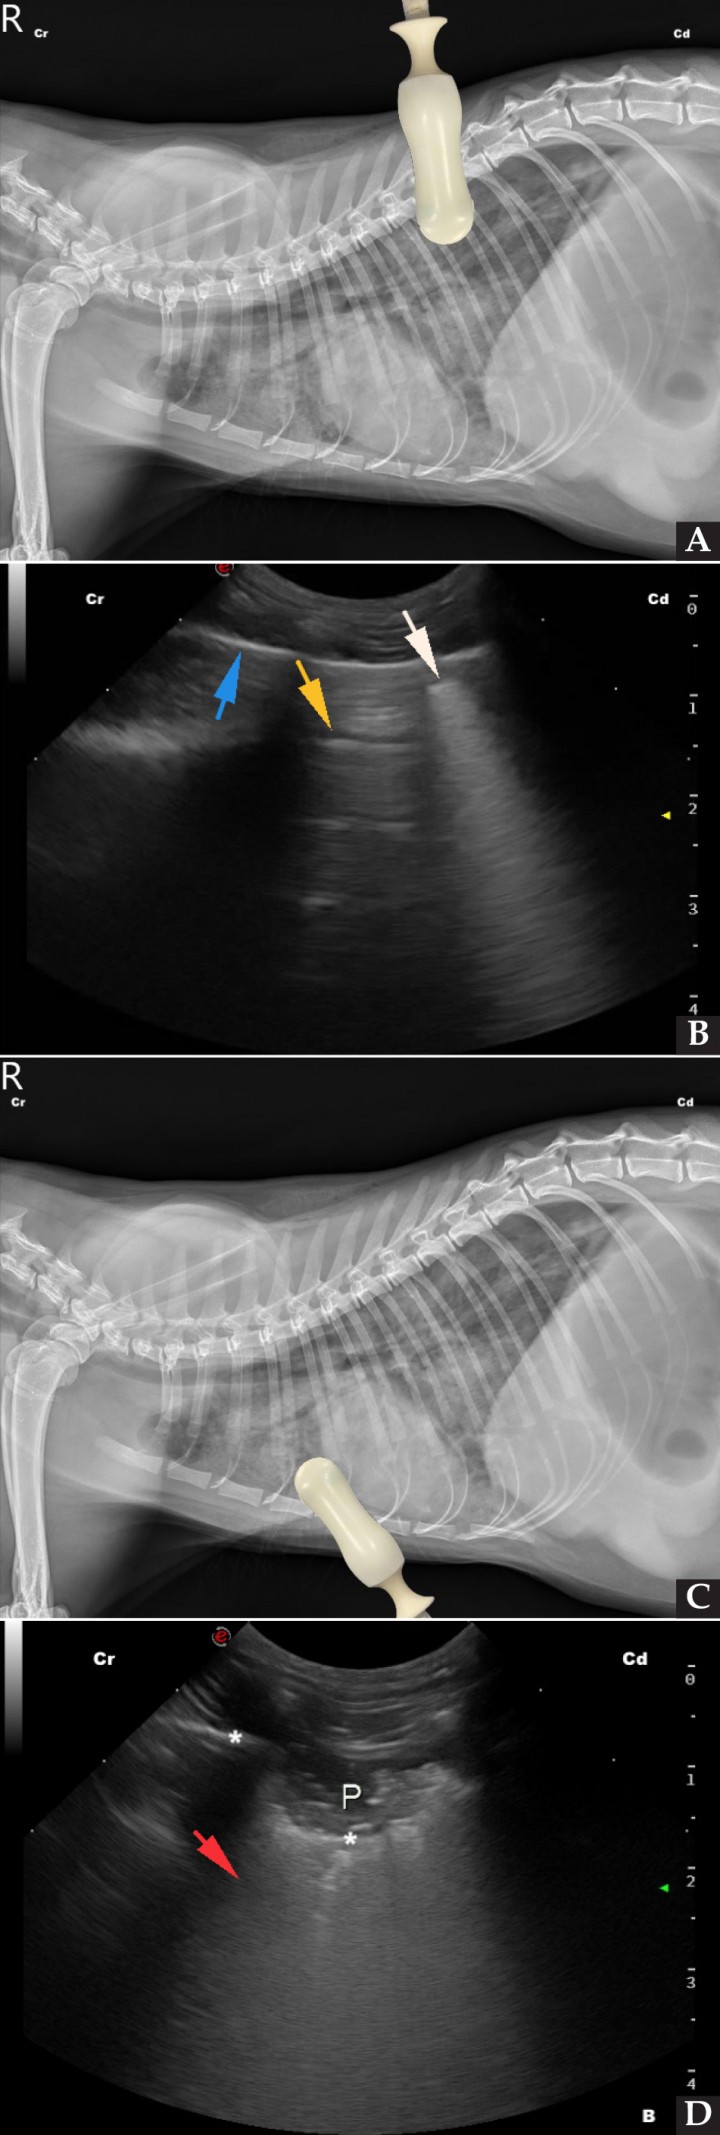

En cuanto a los hallazgos de la T-FAST, en condiciones normales en ambas proyecciones DC debemos observar las denominadas líneas A, aquellas líneas horizontales hiperecoicas paralelas a la interfase pleura-pulmón o línea PP, resultantes de la reverberación del aire contenido en el borde pulmonar (Fig. 4).[ Boysen S, Lisciandro G: The Use of ultrasound for dogs and cats in the emergency room. AFAST and TFAST. Vet Clin Small Anim 2013; 43: 773-797. [PubMed] ] Por el contrario, si visualizamos las líneas B, que son líneas hiperecoicas verticales fácilmente reconocibles, estaremos ante un pulmón con patología, ya que están presentes en el denominado pulmón húmedo o síndrome intersticial. Las líneas B se extienden desde la línea PP hasta el final de la pantalla, no se atenúan y oscilan como un péndulo con el movimiento respiratorio (Fig. 5).[ Lisciandro G: Abdominal and thoracic focused assessment with sonography for trauma, triage, and monitoring in small animals. J Vet Emerg Crit Care 2011; 21(2): 104-122. [PubMed] , Boysen S, Lisciandro G: The Use of ultrasound for dogs and cats in the emergency room. AFAST and TFAST. Vet Clin Small Anim 2013; 43: 773-797. [PubMed] , Andrea M, Walters A, O’Brien MA, Selmic LE, et al.: Evaluation of the agreement between focused assessment with sonography for trauma (AFAST/TFAST) and computed tomography in dogs and cats with recent trauma. J Vet Emerg Crit Care 2018: 1-7. [PubMed] ] Entre los principales diagnósticos diferenciales que se plantean una vez identificadas, cabe destacar el edema pulmonar (de origen cardiogénico o no), inflamación supurativa o contusión pulmonar en caso de pacientes traumatizados.[ Lisciandro G: Abdominal and thoracic focused assessment with sonography for trauma, triage, and monitoring in small animals. J Vet Emerg Crit Care 2011; 21(2): 104-122. [PubMed] , Boysen S, Lisciandro G: The Use of ultrasound for dogs and cats in the emergency room. AFAST and TFAST. Vet Clin Small Anim 2013; 43: 773-797. [PubMed] ]

<p>(<strong>A</strong>) Radiografía lateral derecha de un gato con edema pulmonar no cardiogénico, con la colocación de la sonda ecográfica en el punto de valoración del cuadrante DC. (<strong>B</strong>) Imagen ecográfica del cuadrante DC del mismo paciente, donde se aprecian líneas B o pulmón húmedo (flecha blanca), líneas A o pulmón sano (flecha amarilla) y línea PP (flecha azul). (<strong>C</strong>) Radiografía lateral derecha del mismo paciente con la colocación de la sonda ecográfica en el punto de valoración del cuadrante PH. (<strong>D</strong>) Imagen ecográfica del cuadrante PH, donde se puede observar la presencia de una línea B ancha (flecha roja), así como parte del parénquima pulmonar consolidado (P), generando como consecuencia el signo de escalón (asteriscos). Cr: craneal; Cd: caudal.</p>

(A) Radiografía lateral derecha de un gato con edema pulmonar no cardiogénico, con la colocación de la sonda ecográfica en el punto de valoración del cuadrante DC. (B) Imagen ecográfica del cuadrante DC del mismo paciente, donde se aprecian líneas B o pulmón húmedo (flecha blanca), líneas A o pulmón sano (flecha amarilla) y línea PP (flecha azul). (C) Radiografía lateral derecha del mismo paciente con la colocación de la sonda ecográfica en el punto de valoración del cuadrante PH. (D) Imagen ecográfica del cuadrante PH, donde se puede observar la presencia de una línea B ancha (flecha roja), así como parte del parénquima pulmonar consolidado (P), generando como consecuencia el signo de escalón (asteriscos). Cr: craneal; Cd: caudal.